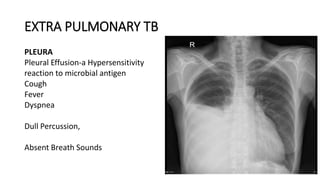

PLEURA

Pleural Effusion-a Hypersensitivity

reaction to microbial antigen

Cough

Fever

Dyspnea

Dull Percussion,

Absent Breath Sounds